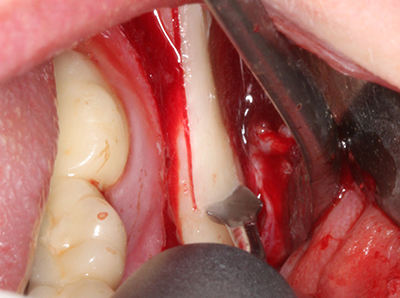

Quando le procedure chirurgiche vengono eseguite sull'osso nelle immediate vicinanze di strutture sensibili, come vasi sanguigni o nervi, gli strumenti rotanti pongono un rischio significativo di lesione iatrogena. I dispositivi piezoelettrici possono essere utili per la preparazione delle coperture ossee e la rimozione del tessuto duro in prossimità dei nervi, in particolare per la loro esposizione dopo una lesione iatrogena, ma anche durante la lateralizzazione dei nervi per le procedure di resezione e ricostruzione o il posizionamento di impianti (figg. 17-20). Il contatto leggero tra puntina piezoelettrica e nervo non causa generalmente danni, ma se si procede senza prestare attenzione con movimenti a sega o raccordi con residui di substrati ossei possono verificarsi danni al nervo temporanei o anche permanenti. Il rischio di danno, tuttavia, è considerato sostanzialmente inferiore al rischio presente utilizzando seghe o frese (Pereira, Gealh et al. 2014).

Fig. 18: preparazione di una copertura corticale con sega piezoelettrica per osso (Piezomed, W&H).

Fig. 19: sito chirurgico dopo neurolisi e rimozione dell'osteoma.

Fig. 20: la copertura ossea rimossa viene riadattata e fissata con una vite per osteosintesi (KLS Martin, Tuttlingen).